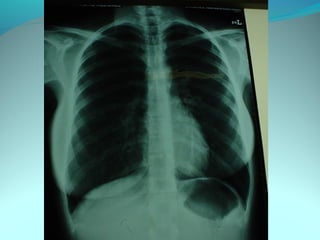

Cliché normal